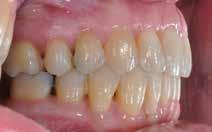

Den kliniske undersøgelse viser harmoniske ekstraorale sagittale forhold med skeletalt dybt bid (Fig. 1A, D). Hendes smil er alderssvarende med en eksponering på 8/10 af overkæbeincisiverne, mens smilets bredde er smalt med synlige mørke laterale rum (Fig. 1D). Underkæbeincisiverne er synlige under tale. Der ses neutrale okklusale forhold ved hjørnetænderne og neutrale pladsforhold i overkæben, men udtalt trangstilling i underkæben især lokaliseret i regio 1-1 (Fig. 1C).

Sliddet klassificeres som grad 2 (moderat tandslid) på de centrale incisiver i overkæbe og underkæbe. Det kan anses som patologisk, da det er atypisk for patientens alder, giver anledning til smerte/ubehag, og giver patienten et æstetisk problem. Der ses infraktioner af overkæbeincisiverne. Der ses endvidere en udtalt Spee-kurve i underkæben og ingen interincisal afstøtning på 2-2 med let ganepåbidning.

Røntgenanalyse viser fravær af -6 samt et velholdt tandsæt uden tegn på sygdom. Profilrøntgenbilledet viser et skeletalt

dybt bid, men normal inklination af fortænder i over- og underkæbe (Fig. 1B).

Fig. 5. A, B. Smil og kæbeforhold før og efter. Et bredere smil med korrektion af de laterale mørke rum. C-F. Harmonisk hældning af overkæbe- og underkæbeincisiver, rekonstruktion af den tabte tandsubstans efter nivellering af gingivaniveau og optimal bukko-lingval placering til direkte plastbehandling.

5. A, B. Smile and jaw relationships before and after. A wider smile with correction of the lateral dark spaces. C-F. Harmonious inclination of the upper and lower jaw incisors, reconstruction of the lost tooth substance after leveling the gingival level, and optimal bucco-lingual positioning for direct plastic treatment.